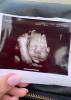

Я 2 дня назад ходила на 3 скрининг, малыш просто взял и отвернулся лицом в сторону моего позвоночника. Чувствую надо было идти с 30 по 31 неделю, ни одного снимка не сделали 😭

С 25 по 30, лучше в 25 недель. Я во вторую беременеть пошла в 28, врач сказала, что малышка уже отвернулась и не получится посмотреть лицо 🥲

С 32 по 34 неделю